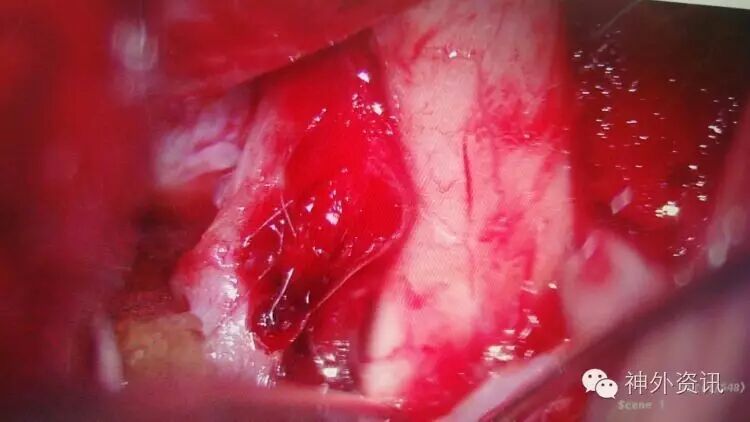

术中见颈动脉前壁局部为血块覆盖,分离血块見局部血管壁正常结构破坏,似单层红色保鲜膜,累及管壁周径约1/5~1/4,IcA后方见脉前、后交通A发出,包裹术无法完成!

术中阻断IcA颅外段与同侧A1,采用一枚“L”型异形夹顺利夹闭BBA,后方脉前A通畅!